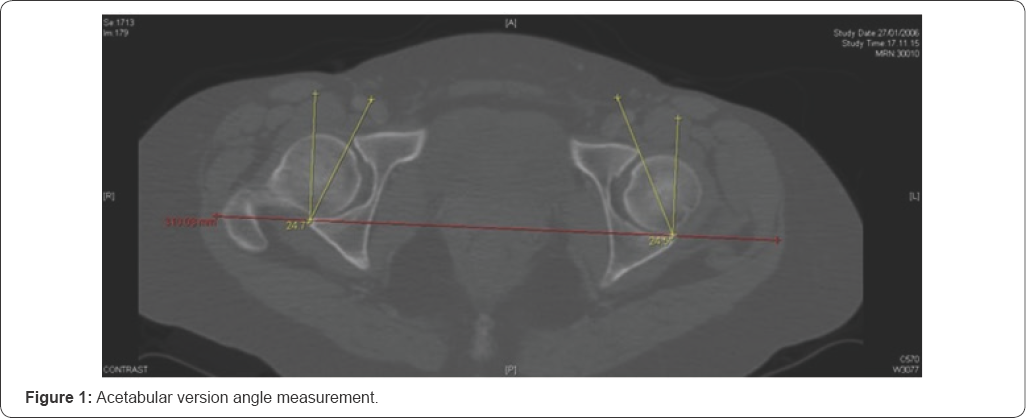

We obtained 44 relevant patients, 25 females and 19 males. On each one of the 88 hip joints we made the following measurements and observation: acetabular version angle, center edge angle, presence or absence of crossover sign. Version angle was evaluated on the orthogonal plane where the acetabulum cup is deeper, with two lines: the first one passing through the anterior and posterior rim of the acetabulum and the second one is perpendicular at the line passing through posterior acetabular rim bilaterally (Figure 1). The presence or absence of acetabular crossover sign was evaluated using the transparent 3-dimensional pelvis model, drawing the acetabular rim and checking if the anterior margin was crossing the posterior margin (Figure 2).